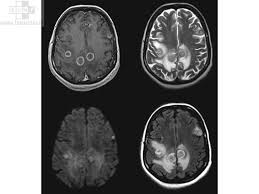

On sait que l'IRM n'a aucun effet biologique, que l'échographie, dans la limite de son utilisation habituelle, ne présente pas de danger. En effet, le spécialiste déplace la sonde rapidement; ne reste pas longtemps sur un même organe à étudier. Il limite ainsi le risque d'exposition et d'augmentation de la température néfaste aux tissus. La scintigraphie, comme les exemples précédents, ne présente aucun risque non plus.

Les seuls problèmes que peuvent rencontrer le patients est une allergie aux produits utilisés pour l'examen ou des effets secondaires liés aux DMI (Dispositif Médical Implanté) qu'il possède.